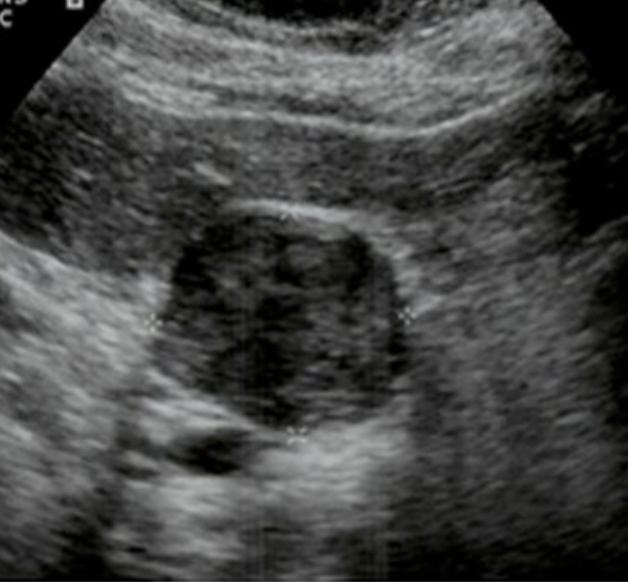

Simple Renal Cyst → common lesion of kidney, fluid-filled sac (benign, Bozniak 1)

clinical hx: incidence increases with age (50+), uncommon in children

s/sx: asymptomatic

2D US: anechoic, well-defined smooth, thin wall, round or ovoid, posterior enhancement

color doppler: avascular

DDX: complex cyst